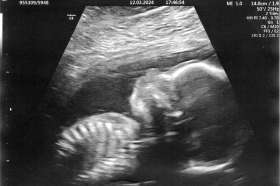

Tomášek - ještě v bříšku

2023-09-26